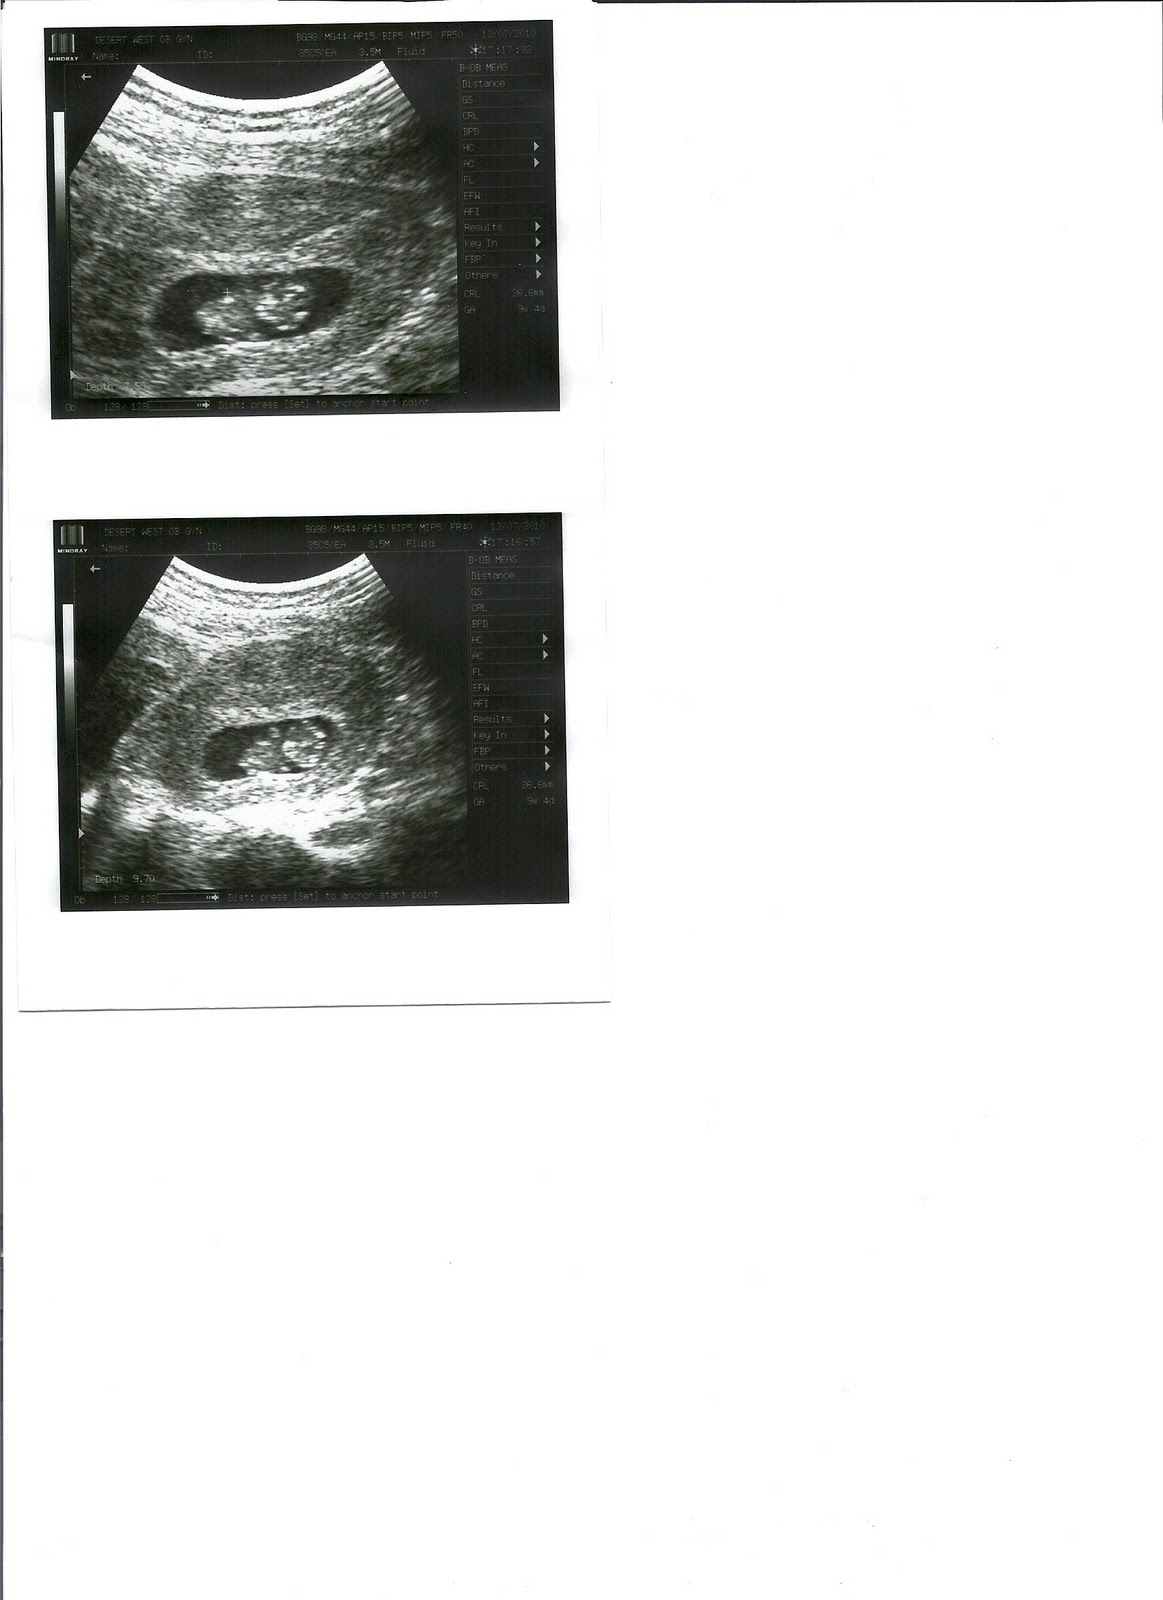

So here goes my first "weekly update". Today I have officially made it to 16 weeks. That just seems crazy. The first trimester flew by!

•How far along?: 16 weeks!

•What I'm looking forward to: Right now, our anatomy scan on February 11th. I can't wait to see our little one again and of course find out if this is a little boy or girl!